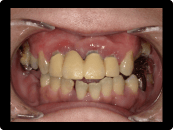

歯周病の治療例

奥歯の重度歯周病は保存困難のため抜歯してインプラント治療。残す歯は歯周病中等度であったため、歯周基本治療歯周外科治療を含めて行い、歯茎からの出血などはなくなった。

BEFORE

AFTER

症例概要

年代・性別

50代 女性

主訴

全体の歯茎から出血する、奥歯が揺れて噛めないことを主訴に来院されました。

治療内容

全顎歯周外科治療(保険治療)+奥歯インプラント治療4本

治療期間

6ヶ月

治療のリスク

歯肉退縮のリスクがあります

治療費用

約160万円